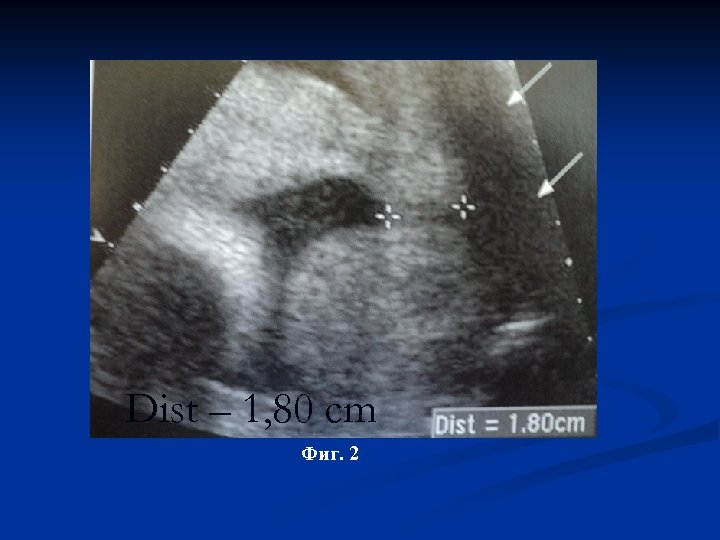

Dist – 3, 43 cm Фиг. 1